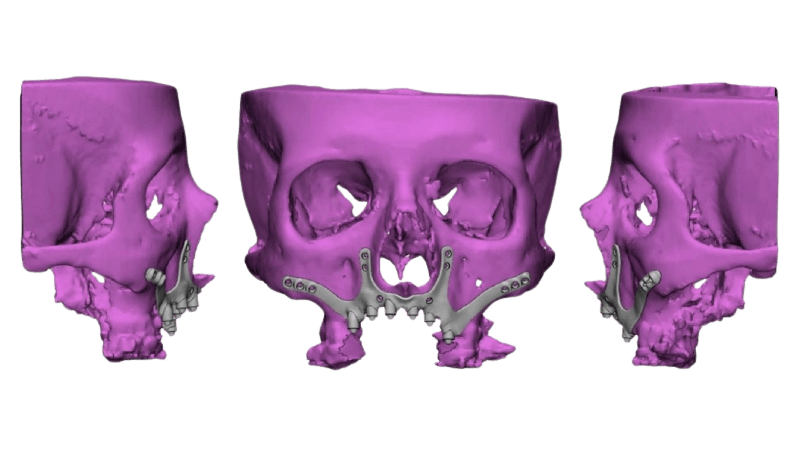

La introducción de la tecnología digital en odontología ha representado un avance significativo en nuestra práctica, y particularmente valioso en la optimización del tiempo de tratamiento, transformando la forma en que llevamos a cabo diversos procedimientos. A través de la tomografía computarizada de haz cónico (CBCT) y modelos 3D intraorales obtenidos mediante escáner intraoral, se recopila la información para que los softwares conozcan las dimensiones reales del paciente y puedan diseñar una estructura que se ancle al hueso remanente y, a su vez, pueda sostener prótesis fijas en rehabilitaciones parciales o totales. Estos implantes se fabrican con modelos hechos con impresoras 3D y sinterización láser directa de Titanio (DMLS), simplificando y optimizando nuestras prácticas.

- Solución a medida: Diseñados y fabricados con tecnología 3D para adaptarse a la anatomía ósea del paciente, permitiendo una mayor precisión y ajuste.

- Mayor superficie de contacto: Distribuyen mejor las fuerzas de masticación, reduciendo el riesgo de reabsorción ósea y mejorando la estabilidad a largo plazo.

- Menor riesgo de complicaciones: Al no insertarse en el hueso, se minimiza el riesgo de daño a nervios o vasos sanguíneos, convirtiéndolos en una opción más segura para pacientes con ciertas condiciones médicas.